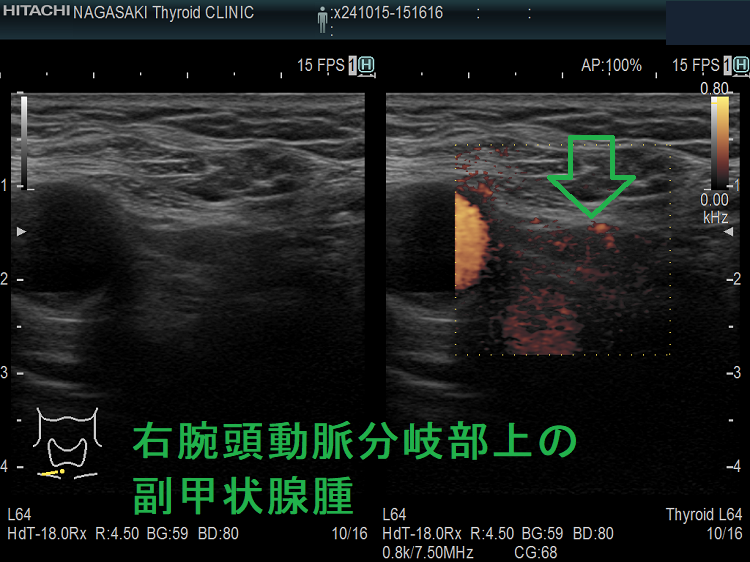

(➸)原因となる副甲状腺腺腫、副甲状腺癌、副甲状腺過形成をデジタルハイビジョン超音波診断装置で診断。エコーでは、甲状腺とのインピーダンスの違いにより、甲状腺-副甲状腺境界部に線状高エコーが生じます(右図の↓)。内部は中心血流を認め、リンパ節でないのが分かります。

ケース② 右腕頭動脈分岐部上の副甲状腺腫